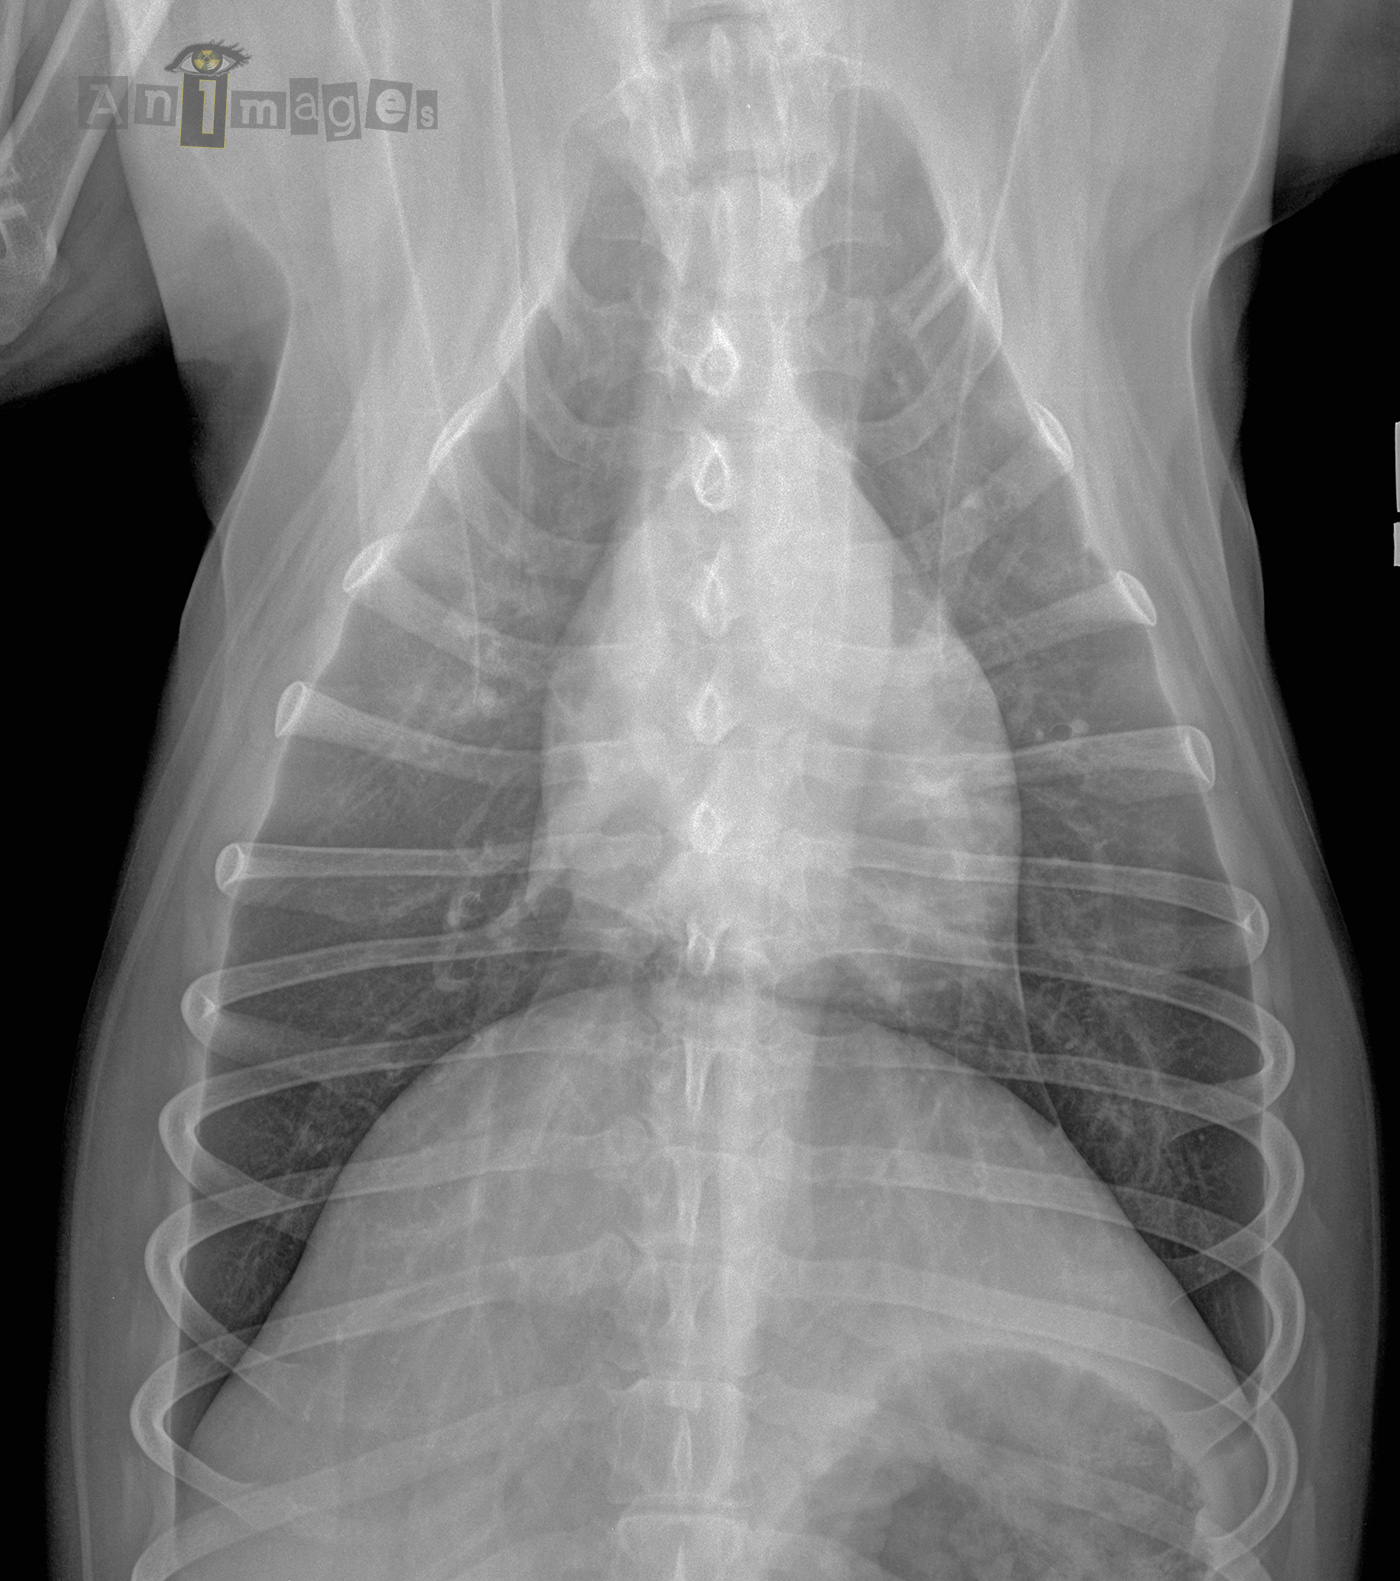

Dorsoventrale – 4 mois plus tard